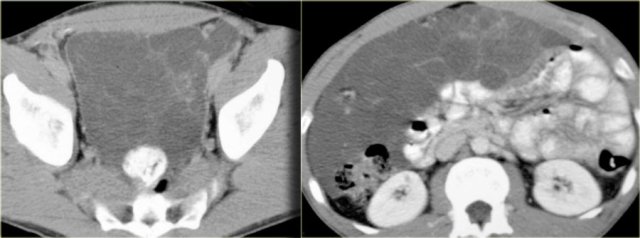

Mesenteric fibromatosis - Desmoid (3)

On the left again a more typical case with a low density tumor located in the greater omentum (upper image) and the gastrosplenic ligament (lower image).

On the left an unusual location, because normally there is no mesentery deep in the pelvis.

This patient had familial adenomatous polyposis.

A total colectomy with J-pouch of the ileum was performed.

Now accompanying that J-pouch is mesentery in which mesenteric fibromatosis has developed.

Notice the low attenuation foci or bands of myxoid stroma within the tumor.

In familial adenomatous polyposis the mesenteric fibromatosis is almost always post operative and occurs at the operative sites.

It frequently occurs at multiple sites including abdominal wall fibromatosis.

These cases can be very aggressive.

It usually comes back and when it does, it comes back as a more aggressive tumor.

Therfore these patients are treated as conservatively as possible.